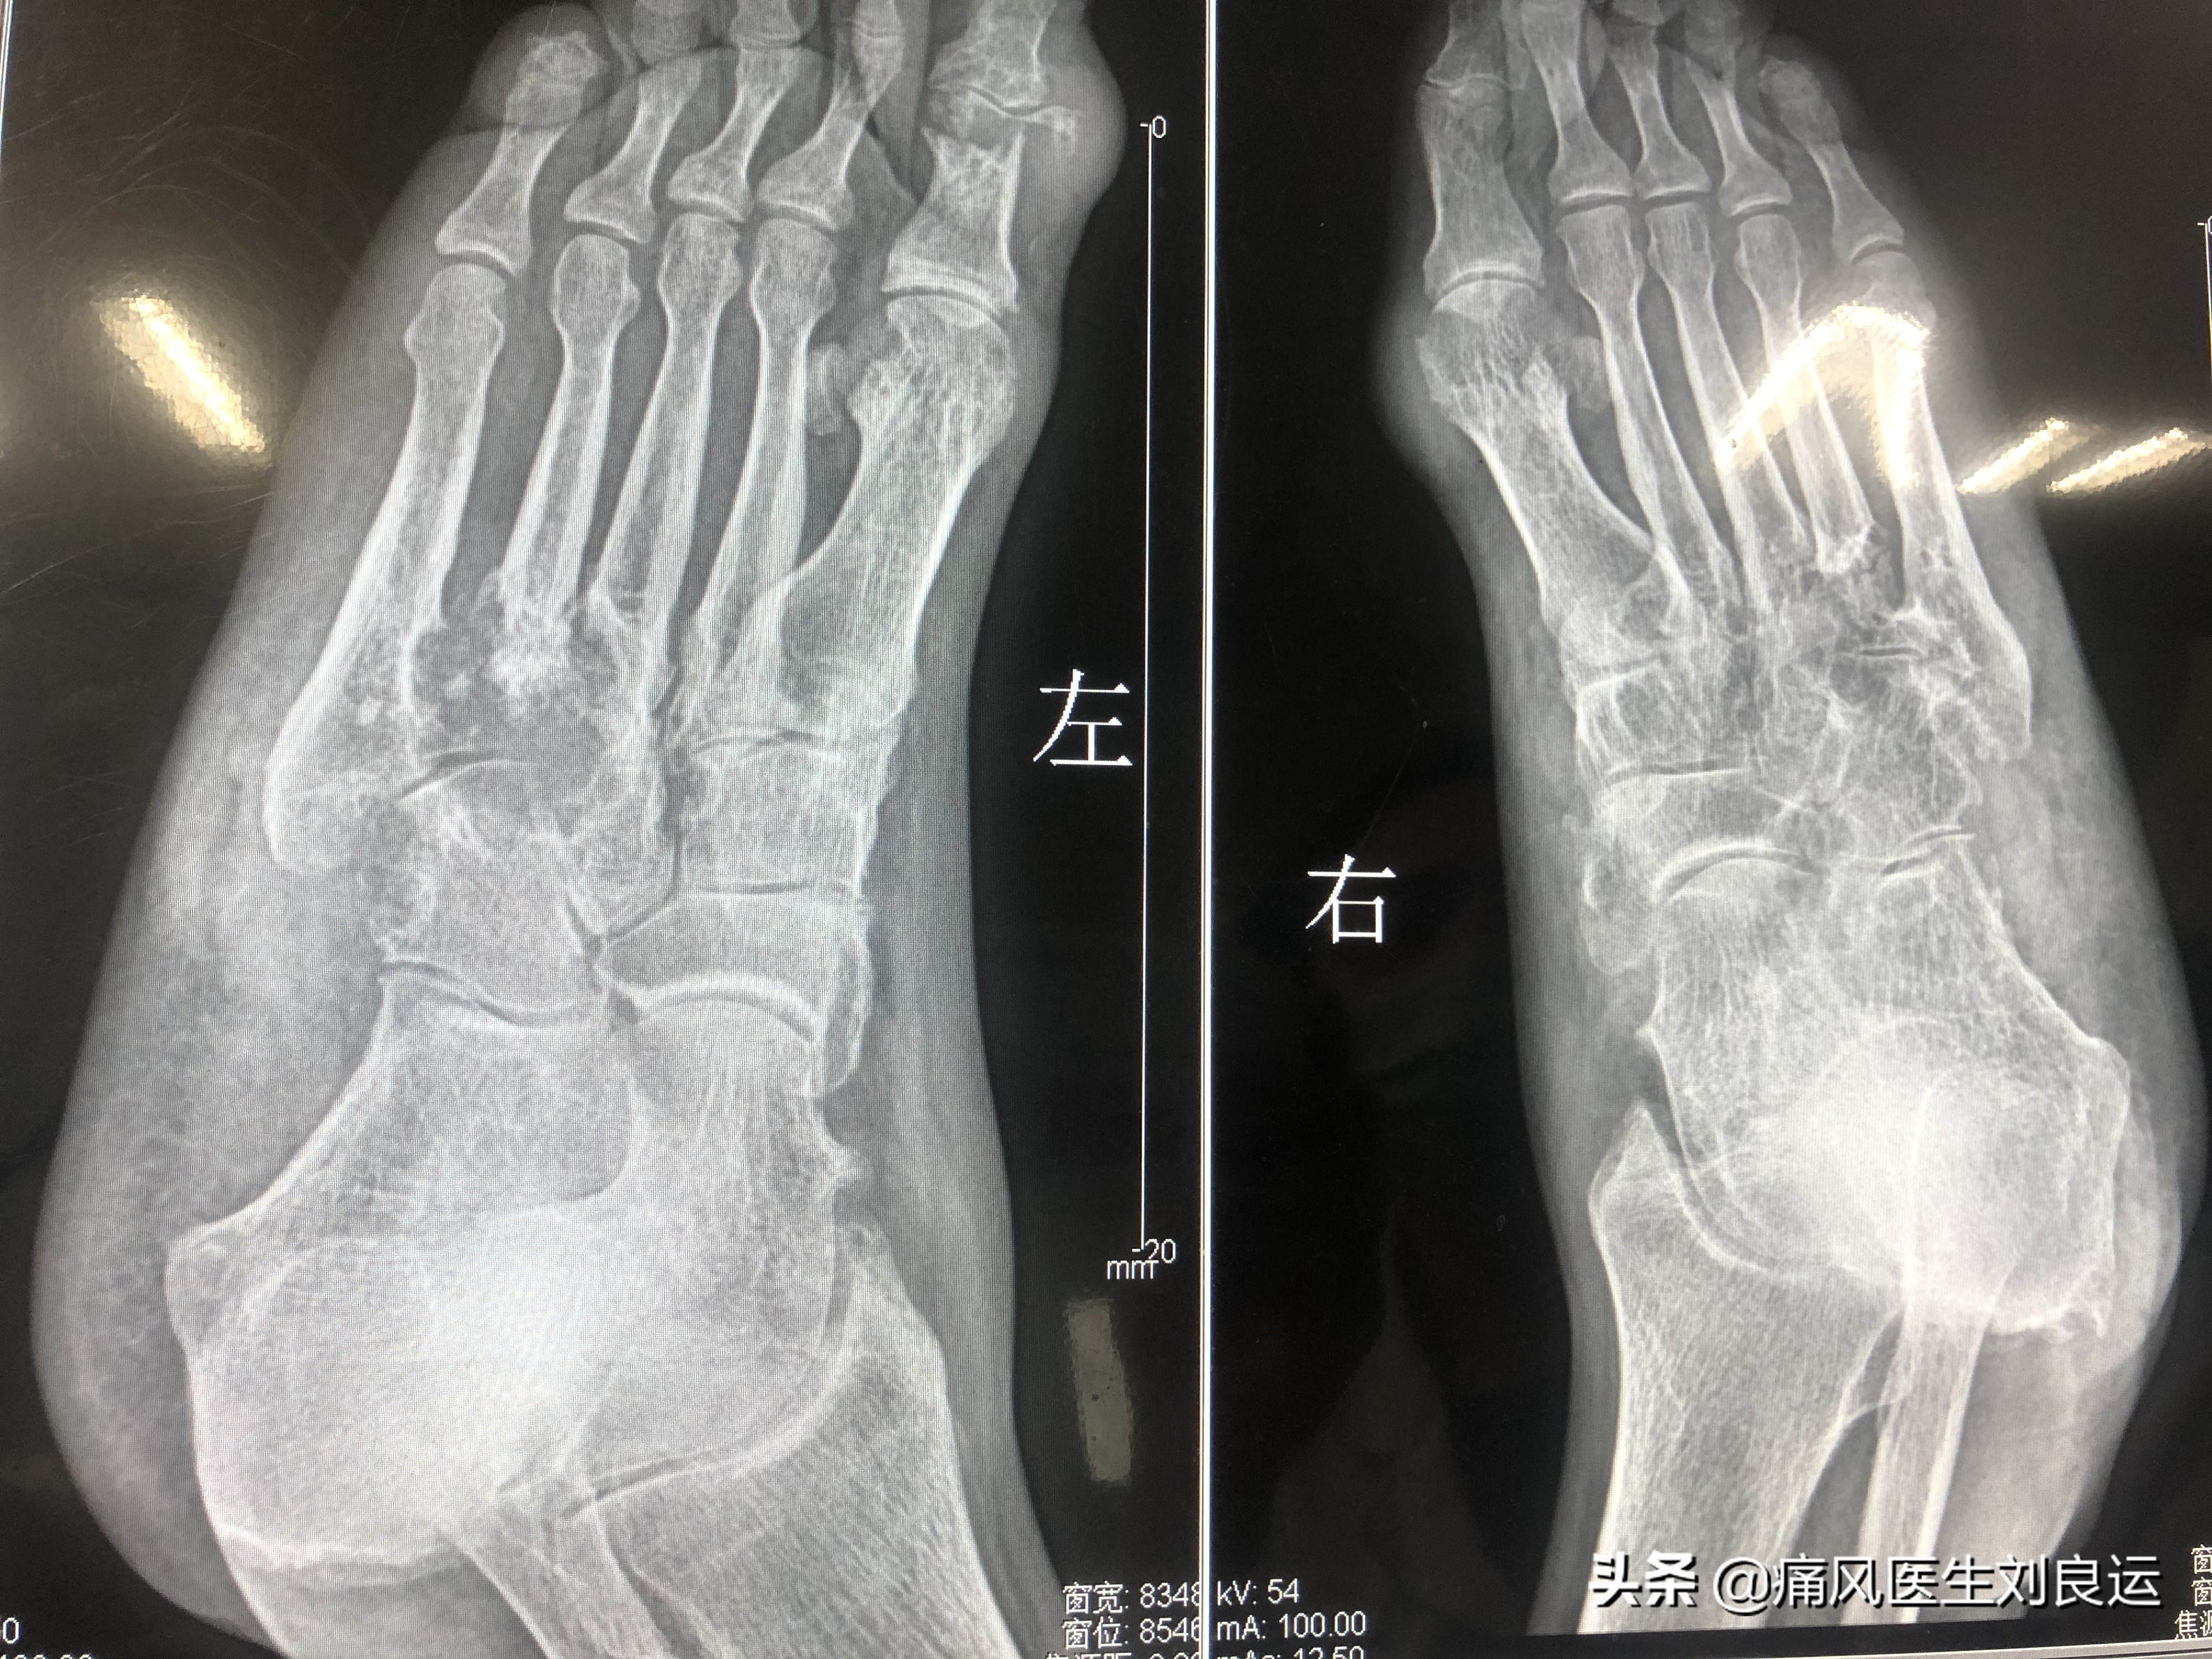

痛风石对脚部的侵蚀,可以慢慢的将整个脚的骨头都“吃掉”